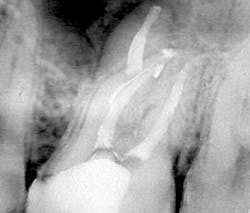

Why does 3-D obturation of root canal systems matter? The biologic rationale for 3-D obturation (root canal systems filled to their full apical and lateral extents) is that we never know for certain whether we have killed every bacterium in any given root canal system. If I have failed to achieve sterility in a root canal system—which is always a possibility despite my best efforts—I can still achieve successful healing if I entomb any remaining infectious agents with sealer and gutta-percha (figure 1). Herbert Schilder, DDS, was the first to describe a predictable obturation method—his Vertical Condensation Technique, also described as the vertical compaction of warm gutta-percha (1)—that could fill any lateral canal complexity that was cleaned beforehand.

Figure 1: Maxillary molar with an MB2 canal that bifurcated, mid-root, from the MB1 canal, made a 90-degree turn, and bifurcated again in its apical 3 mm. A canal form such as this is unlikely to be known before or during root canal treatment, presenting more than 7 mm of canal space that was unnegotiable, unshaped, and most certainly not sterilized during irrigation procedures. This is a case that succeeded only because the inevitable bacterial remnants were entombed by filling material during 3-D obturation.